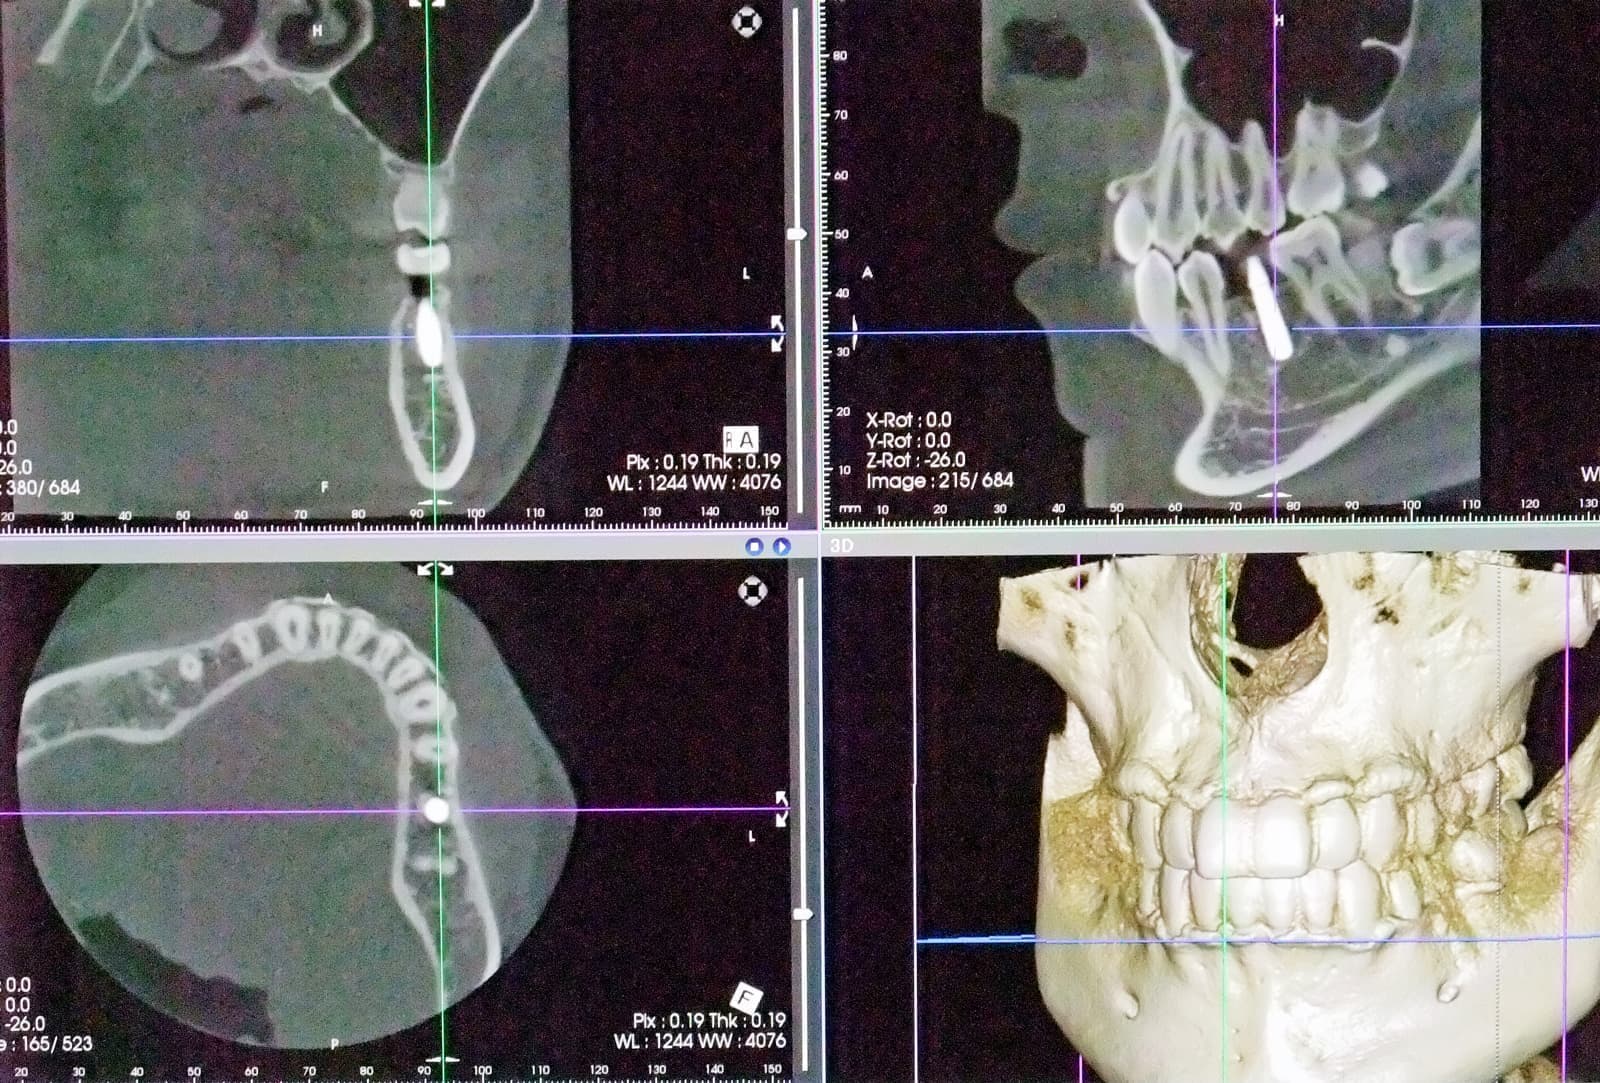

CT3Dデジタルレントゲン

img_9991.jpg dsc01415.jpg dsc01410.jpg ct1.jpg ctga_20201009231644597.jpg cth.jpg

患者様に負担をかけず、現状を詳しく把握すること!

CTのメリットは、これまでの歯科用エックス線検査よりもはるかに多くの情報を得ることができることです。

その結果、より正確な診断・治療を行うことができるだけではなく、より安全な治療を提供することができます。

また、被曝量について気にされる方も多いと思いますが、通常の医科用CTに比べ歯科用CTは、はるかに被曝量(1/10〜1/50)が少なく、そして今回導入したCTは被曝量の低減について以前より更に努力をされているメーカーのレントゲンです。